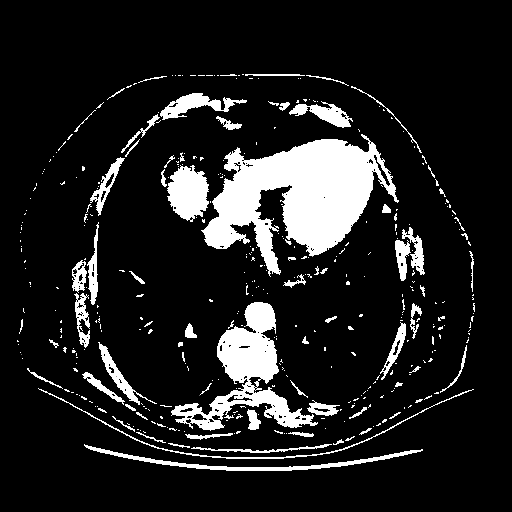

Generated VENOUS CT scan (A→B translation)

Full window (WL 1023.5, WW 4095 β†’ Low βˆ’1024, High +3071)

Actual HU range: [-1024.0, 3071.0]

Lung window (WL -600, WW 1500 β†’ Low βˆ’1350, High +150)

Actual HU range: [-1350.0, 150.0]

Mediastinum window (WL 40, WW 400 β†’ Low βˆ’160, High +240)

Actual HU range: [-160.0, 240.0]